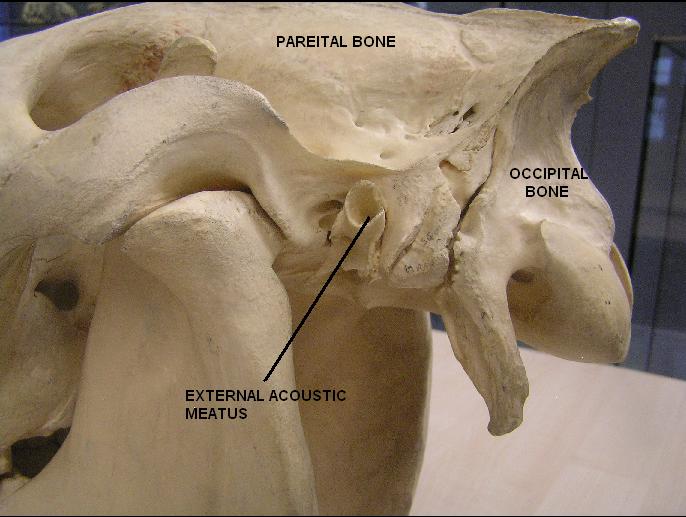

Анатомия сосцевидного отростка